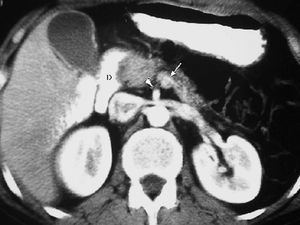

La pancreatitis del surco, región anatómica situada entre la cabeza del páncreas, duodeno y colédoco, es una lesión fibrosa que oblitera el plano graso de separación entre la pared duodenal y el páncreas. Puede provocar una estenosis de la luz duodenal y del colédoco. Radiológicamente simula un cáncer pancreático, manifestándose en la ecografía como una lesión hipoecoica y en la TC como imagen hipodensa, hipovascular en la fase precoz, con realce tardío18,19 (fig. 12).

Fig. 12--Pancreatitis del surco. Tomografía computarizada con contraste intravenoso. Lesión hipodensa (*), mal definida, que oblitera el plano graso normal entre páncreas (P) y duodeno (D) y con escaso realce.